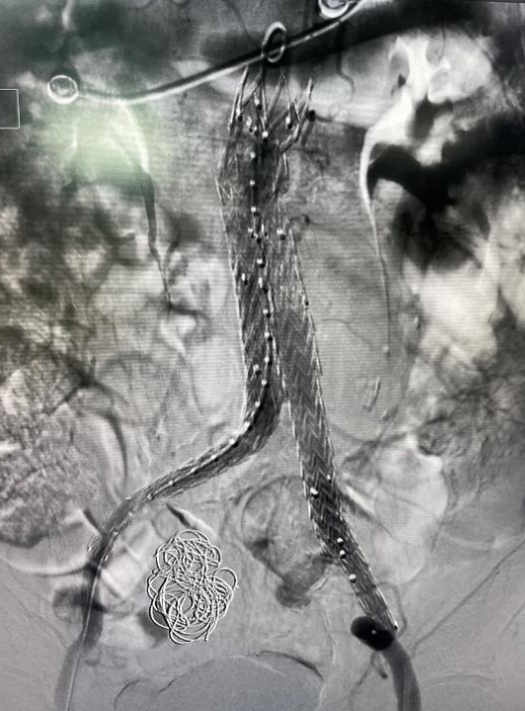

術(shù)后造影圖

術(shù)后,李伯再次造影提示支架貼合良好,且未發(fā)現(xiàn)內(nèi)漏、周圍臟器血管閉塞等并發(fā)癥。次日李伯就能下床活動,行走自如。目前,西電集團(tuán)醫(yī)院神經(jīng)內(nèi)科介入團(tuán)隊已成功為四名患者“拆除”腹腔“炸彈”。